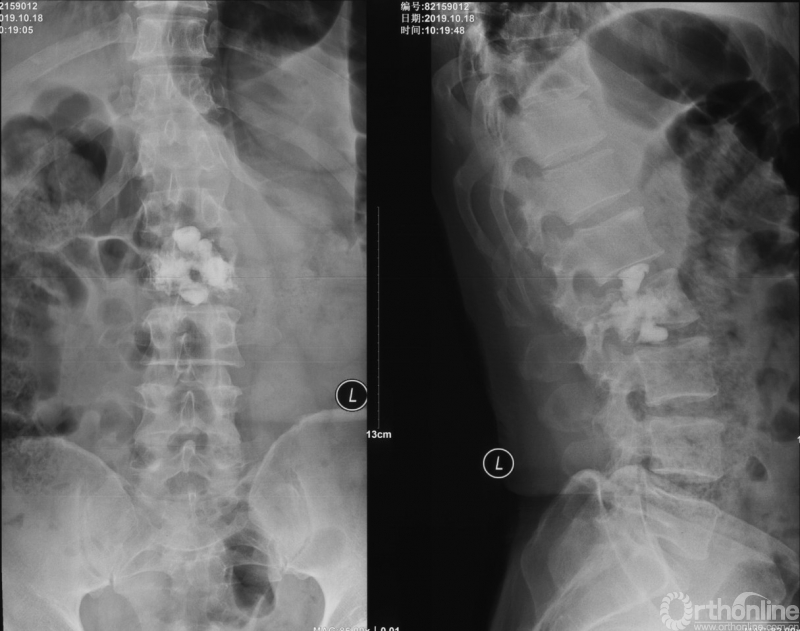

为进一步减少创伤,获得更好的综合疗效。骨采用经皮内固定的微创杂交技术,暨经皮内固定结合小切口分离手术,手术失血900ml,术后7天出院。

术中资料

手术视频:http://res.orthonline.com.cn/video/SSZH.mp4